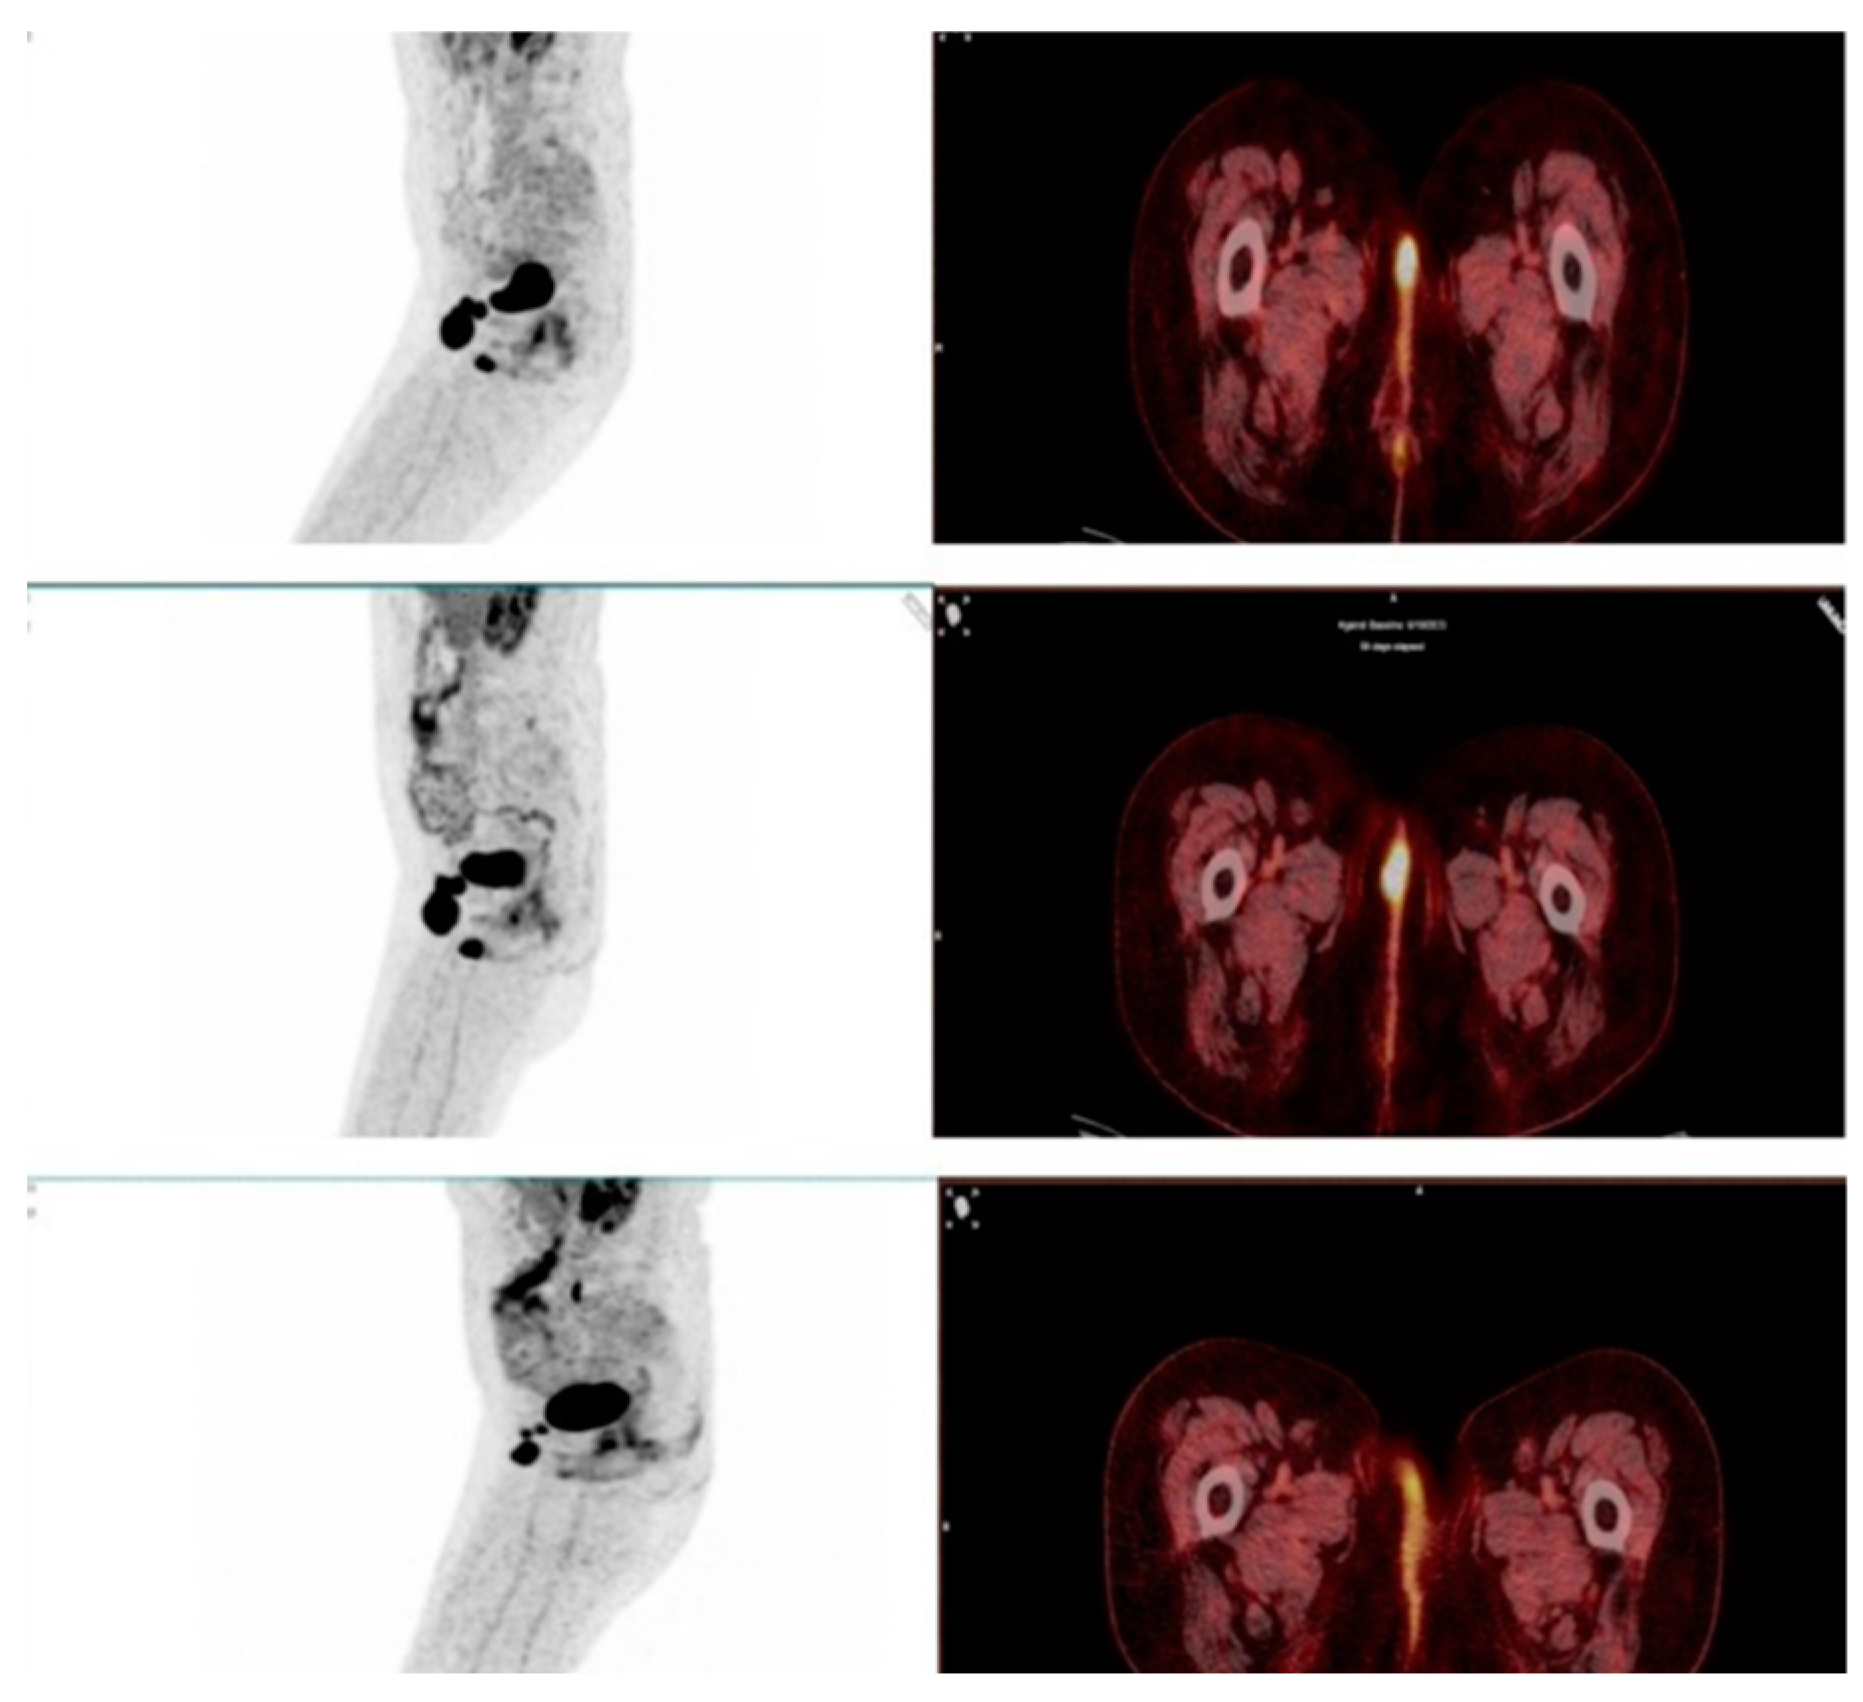

This study evaluated the role of F-18 FDG PET/CT in assessing therapy response in patients undergoing immunotherapy with immune checkpoint inhibitors (ICIs). One of the key findings was the ability of PET/CT to differentiate true progressive disease from pseudoprogression, which remains a major challenge in immunotherapy monitoring. Among the 93 patients, 9 showed stable disease (SD) or partial response (PR) on the required follow-up scans after 6–8 weeks and were therefore classified as pseudoprogression (Figure 4 and Figure 5). The estimated pseudoprogression incidence in our study – 9,7% - aligns with previously reported data. A systematic review and meta-analysis by Park et al. found an overall pseudoprogression incidence of 6% and less than 10%, with slight differences between cancer types, administered ICI and differences coming from the different definitions of pseudoprogression [33]. These results further support our findings and confirm that pseudoprogression remains a relatively rare, but clinically significant phenomenon. Failing to correctly identify pseudoprogression may result in the premature discontinuation of a beneficial therapy, depriving patients of a potential long-term response.

Figure 4. A case of pseudoprogression. Female patient with metastatic melanoma of the vulva undergoing immunotherapy showed increased size and metabolic activity of the primary tumor mass and metastatic inguinal lymph nodes on the first follow-up scan. Immunotherapy was continued and a confirmatory scan was performed 6 weeks later. It showed a Partial Response to therapy.